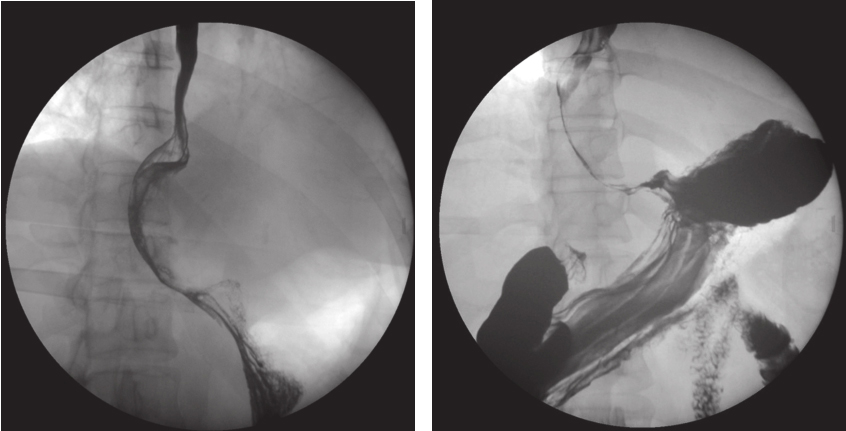

上消化道钡剂造影(图2):食管下段钡剂通过稍缓慢,局部管腔向右推移,管腔充盈欠佳,累及段长约8cm,余管壁柔软,黏膜规则,扩张可。多考虑食管下段外压性改变。

图2 术前钡剂造影